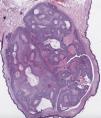

HistopathologyComplete excision of the lesion was performed. Pathologic examination revealed a nonencapsulated polypoid neoformation (Fig. 2) composed of dermal tumor nodules separated by fibrous tracts. The nodules consisted of 2 types of cells: round cells with clear cytoplasm showing a positive periodic acid-Schiff reaction (Fig. 3) and polyhedral cells with round nuclei and slightly basophilic cytoplasm. No mitotic figures or angiolymphatic or perineural invasion were observed. Also present were cysts containing homogeneous eosinophilic material, surrounded by a layer of cuboidal epithelial cells, with no evidence of decapitation secretion.